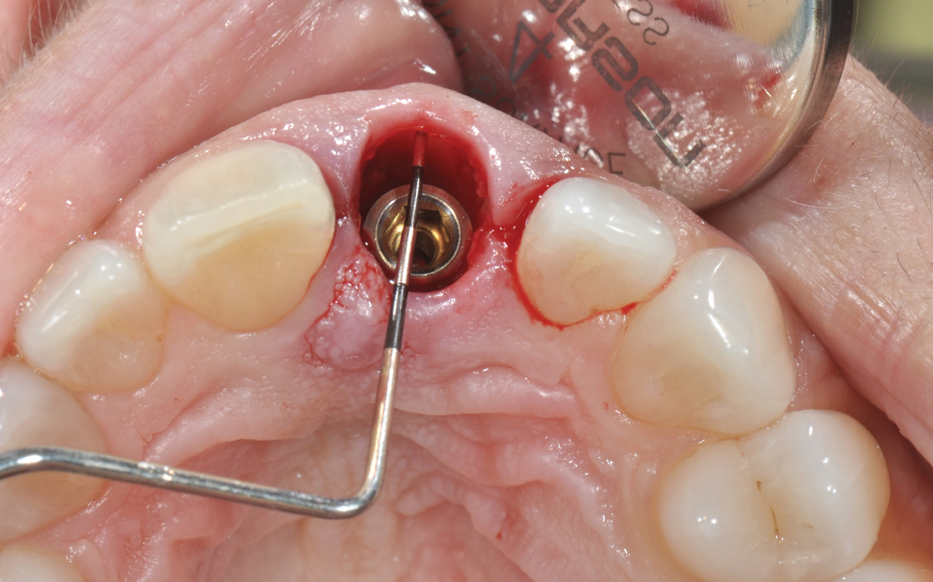

Guided Bone Regeneration

Management of the defect between the implant and socket walls and contour enhancement beyond the facial/buccal socket wall are almost always required in immediate placement approaches. Bone grafting of the residual horizontal defect and, at times, buccal contour augmentation are used to compensate for expected buccal plate changes resulting from extraction, especially when the bone morphotype is thin (Figure 19 through Figure 22). Soft-tissue grafts can be used to further support stable facial tissues, but they will not completely prevent changes in bone volume that are associated with postextraction remodeling (Figure 23 and Figure 24).

(20.) Immediate implant placement. The residual bone defect, which measures approxi-mately 3 mm, was intentionally developed by planning the use of a suitable implant diameter.

Figure 20

(21.) Guided bone regeneration using a collagen membrane and adapted bone graft.

Figure 21

(22.) Prefabricated custom healing abutment. Note the facial cutback to allow for the addition of a connective tissue graft to level the gingival margin with the contralateral dentition.

Figure 22